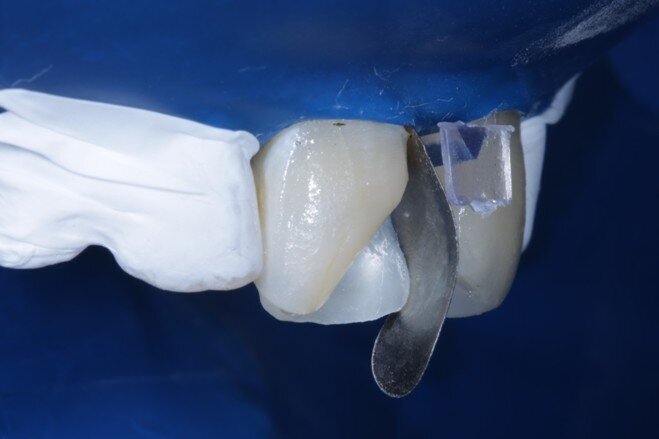

Two weeks later, the shade [ Fig 3 ] stabilized and the teeth were ready for bonding. We observed that the central incisors were still darker than the neighboring teeth. Direct composite veneers were planned with the help of a lab made wax up [ Fig 4 ] and a putty index. Bevels were placed and most of the preparation was in enamel. After the total etch protocol, 5th generation bonding agent was used. 3M Z350XT shades were used for the build up. A2 Enamel shade was used for the palatal shell [ Fig 6 ] and the proximal walls [ Fig 11 ].

Fig 9 Sectional matrix placed vertically

Fig 10 Enamel shade for proximal box layering